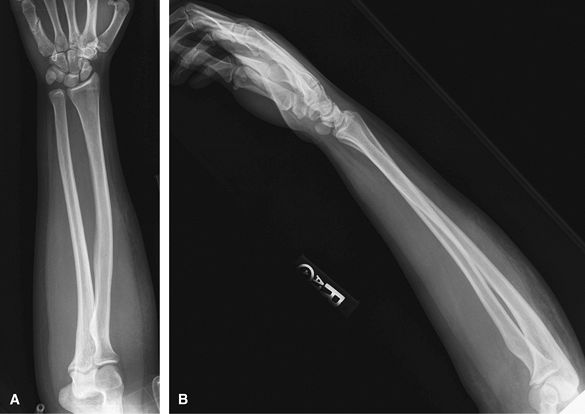

Forearm

Good for trauma, mass, foreign body,

cellulitis/osteomyelitis, or abscess. It is important that the elbow

rotates through 90 degrees between the AP and lateral so that 2

identical views of the ulna are not obtained. Consider US or MRI to

assess for mass or soft tissue injury.

![]() |

Figure 8 (A) AP forearm. (B) Lateral forearm.